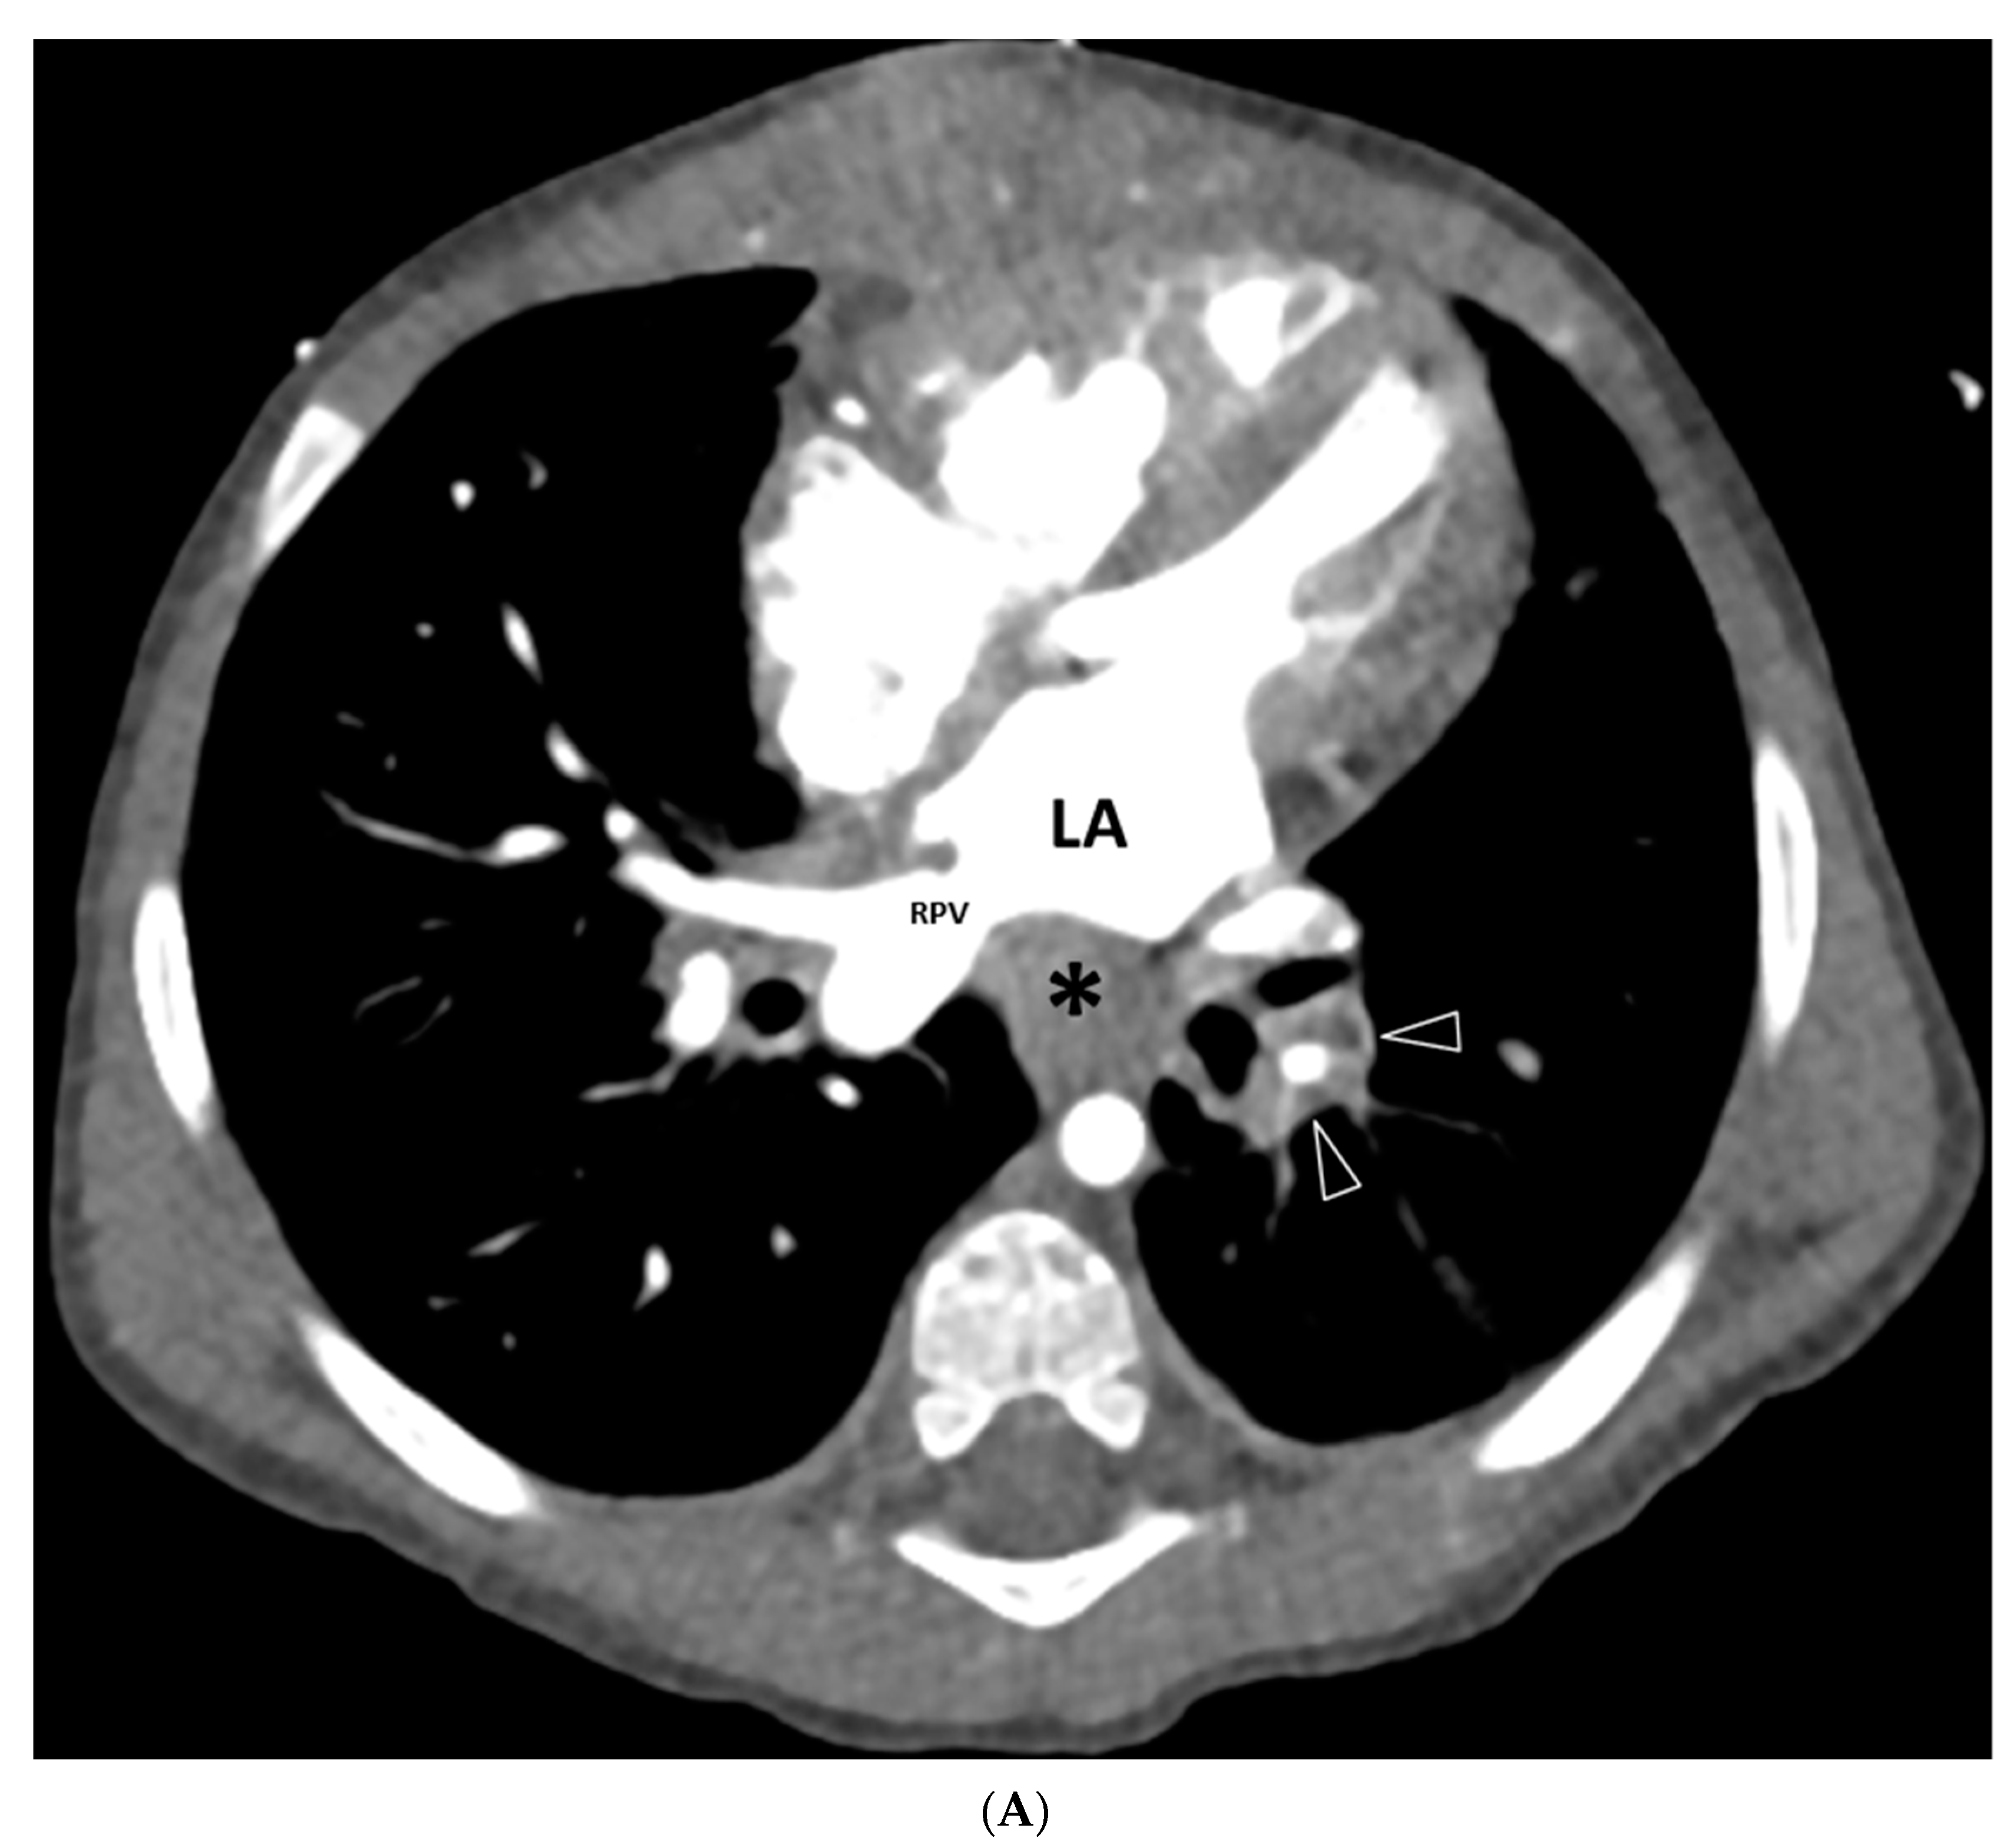

3.2.3. Mediastinal Abnormalities